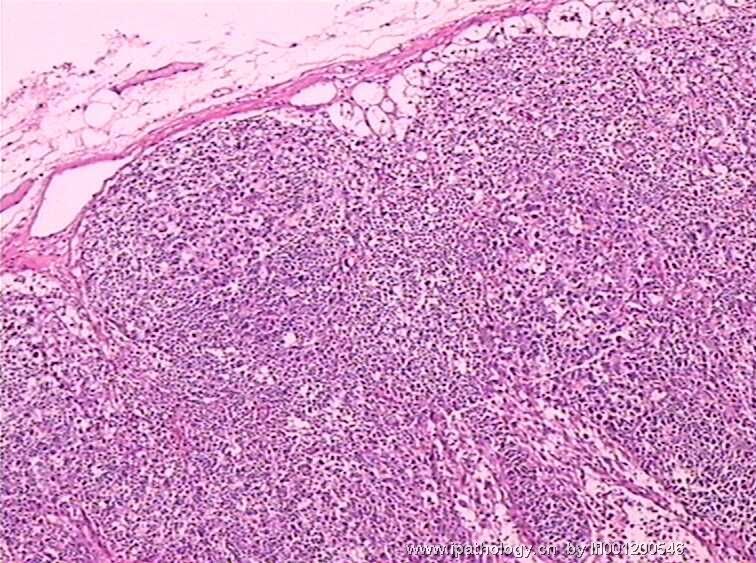

女,45岁,发现颈部多个淋巴结肿大,体查时发现全血细胞减少.取最大的淋巴结送检.

淋巴结结构破坏,有明显异常细胞,结合病史,考虑恶性,淋巴瘤、白血病?不知血片分类怎样?待组化和专家讲解。谢谢!

恶性,考虑淋巴造血系统肿瘤。NHL或白血病。

恶性是肯定,就是要排除转移的恶黑。再考虑原发的非何杰金